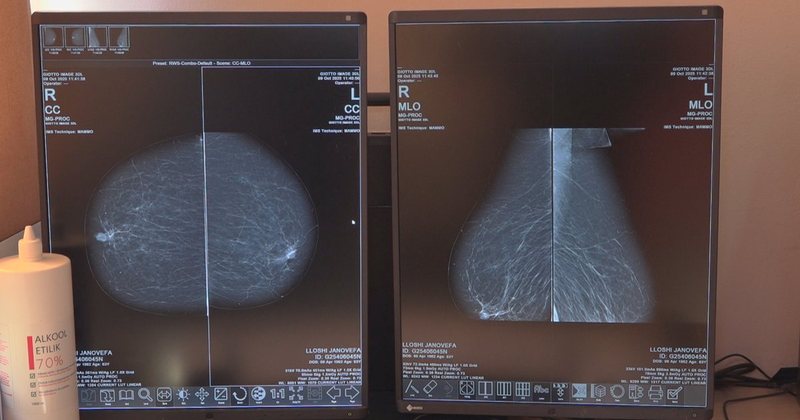

Ndërsa tek femrat më i përhapur është kanceri i gjirit me 800 raste të reja çdo vit. Edhe nga Qendra Spitalore “Nënë Tereza” raportohet rritje e rasteve dhe e shtrimeve nga sëmundjet tumorale.